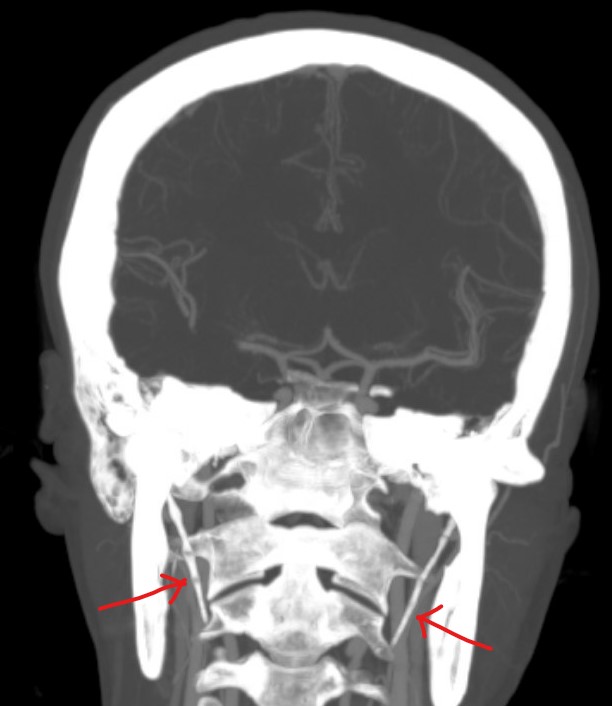

Better imaging for carotid dissection is contrast enhanced CT angiography or MR angiography. The classic sign of dissection on CT or MR is of called a flare. A flare is the narrowed lumen. It looks like a narrow flame. Other findings are the dissection flap or a contrast filled crescent. Sometimes a pseudoaneurysm is visible.

Here is an example. This is a CT of the same patient as the beginning of this article. This CT was performed 3 months later than the other one. Notice there is better flow in the right carotid artery. This points to a healing process of the dissection: